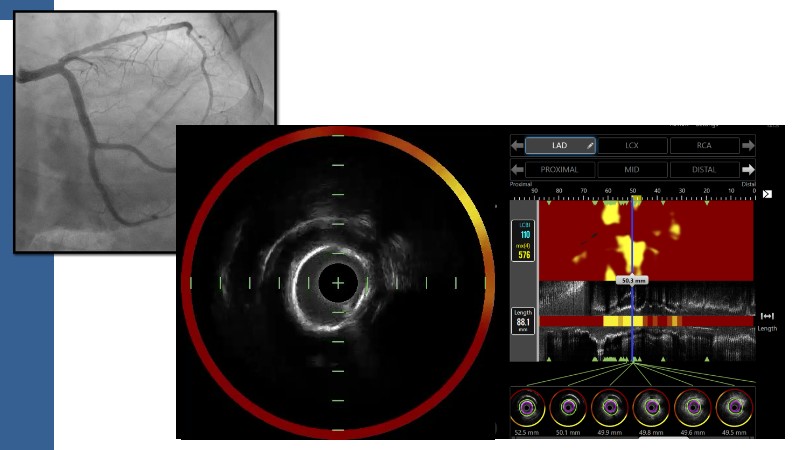

This session explores how near-infrared spectroscopy (NIRS) is redefining PCI by revealing what angiography cannot see. By identifying lipid-rich and vulnerable plaques, NIRS helps anticipate procedural risk and refine decision-making before stent implantation. The session shows how plaque composition, rather than calcium alone, can guide lesion preparation strategies, support safer stent positioning, and improve expansion. Through practical examples, it highlights how integrating NIRS with intravascular imaging and physiology moves PCI toward a more targeted, data-driven, and truly precision-based approach.

- To identify vulnerable plaques: NIRS detects lipid-rich plaques that are invisible to angiography. This allows interventionalists to anticipate complications like distal embolisation or no-reflow and adjust their approach accordingly

- To optimise lesion preparation: when NIRS reveals high lipid burden or calcific nodules, operators can choose atherectomy, intravascular lithotripsy, or specialised balloons to modify the lesion before stenting

- To improve stent placement and expansion: NIRS-IVUS guidance ensures stents are deployed in stable segments, avoiding lipid-rich or heavily calcified areas that may compromise expansion or healing